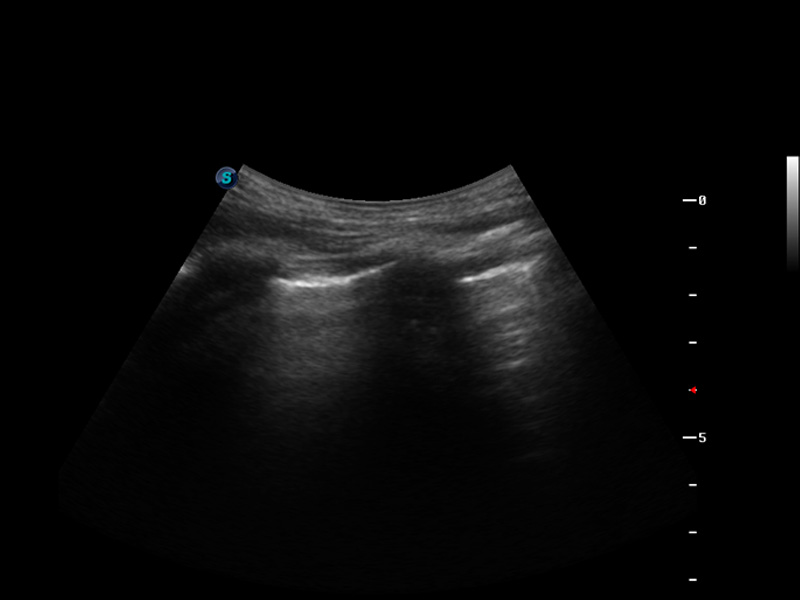

S9便携式彩色多普勒超声诊断仪是竞技宝(JJB)官方网站研发的高端便携彩超设备,外观设计新颖、产品性能卓越。S9在便携超声领域采用了突破传统的触摸屏交互设计,并以先进的软件硬件技术和设计理念,为您带来清晰的图像质量、稳定的工作性能和便捷的操作体验。